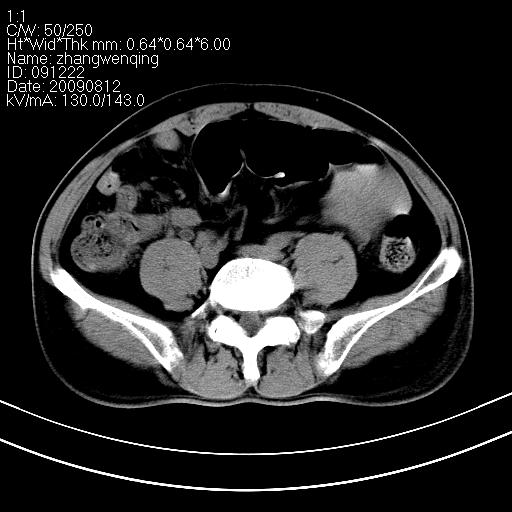

标题: CT21569:M,54Y,右侧中腹部疼痛,IVP示右侧输尿管中下段充盈缺 [打印本页]

标题: CT21569:M,54Y,右侧中腹部疼痛,IVP示右侧输尿管中下段充盈缺

右输尿管下段扩张积水。左下腹部肠管间质瘤不除外。

看不清,应打个增强,右侧输尿管扩张,右侧肠系膜上好像占位。

右侧输尿管扩张.

右侧输尿管扩张积水,考虑结石,最好做个增强除外输尿管占位性病变

右输尿管下段扩张

右侧输尿管扩张积水,最好做个增强除外输尿管占位性病变

右侧输尿管扩张积水,建议增强排除占位。

支持右侧输尿管中下段扩张积水,建议增强排除占位。

右侧输尿管下段扩张,原因待查;建议行进一步检查。

右输尿管下段扩张积水,壁增厚、边缘不光整,考虑炎性改变

ct21569:阑尾腺癌

ct21569和ct21569b(增强)结果:阑尾腺癌,侵犯回盲部及输尿管中段。手术切除部分升结肠、回肠及受侵4cm之输尿管,做回-横结吻合,输尿管支架置放术并吻合,术后病理腺癌,阑尾来源可能性大。